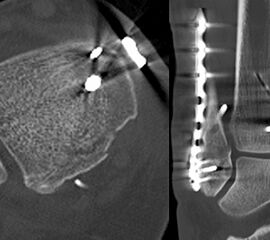

Gardner et al. konnten beispielsweise zeigen, dass die offene anatomische Reposition der Tibiahinterkante der Stabilisierung mittels Stellschraube überlegen war und gleichzeitig mit einer geringeren Rate an postoperativen Fehlstellungen der Fibula in der CT-Kontrolle einherging 2728. Aus Sicht der Autoren ist prinzipiell die Stabilisierung über eine direkte Reposition indiziert, wenn die Größe des Fragmentes dies erlaubt. Bei gleichzeitigem Vorliegen einer Fraktur des lateralen und/oder medialen Malleolus sollte zunächst die Versorgung der des Tibiahinterkantenfragments erfolgen. Dies erlaubt die radiologische Kontrolle der Reposition und Osteosynthese-Lage, welche durch eine zuvor aufgebrachte Fibula-Platte häufig erschwert ist 29. Dafür werden die Patienten in Seitenlage gelagert. Dies erlaubt die direkte Versorgung der posterioren Malleolusfraktur über einen posterolateralen Zugang 30. Das sehr kräftige Periost wird im Frakturverlauf inzidiert und aus den Frakturspalt entfernt, so kann eine anatomische Reposition erfolgen. Entsprechend der Fragmentgröße erfolgt entweder die Versorgung mittels Drittelrohrplatte in Antiglide-Technik oder eine Zugschraubenosteosynthese. Die Versorgung der Fibula-Fraktur gelingt über den gleichen Zugang. Zur Versorgung des medialen Malleolus wird der Patient auf den Rücken umgelagert. Dies kann bei entsprechender Vorbereitung ohne erneutes steriles Abdecken erfolgen. Durch dieses Vorgehen konnte im eigenen Kollektiv die Notwendigkeit einer Stabilisierung der Syndesmose mit Stellschraube/Tight Rope deutlich reduziert werden.